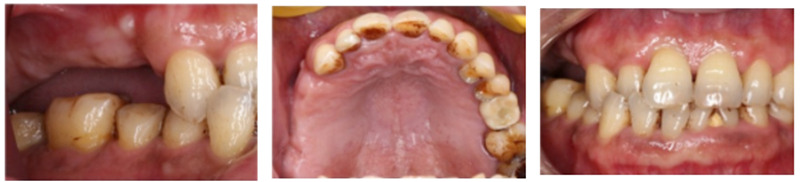

主訴:右側后牙缺失6個月以上,要求種植修復。

現(xiàn)病史: 多顆后牙連續(xù)缺失,未進行活動修復 。

檢查:患者14、15、16、17缺失,無紅腫潰瘍,牙齦情況良好,口腔衛(wèi)生狀況良好。

診斷:14、15、16、17缺失

®石膏模型上進行排牙確定患者咬合關系,取放射阻射材料灌于缺牙區(qū),患者戴著處理過的

配準裝置拍攝術前CBCT。

®根據(jù)CBCT中牙冠顯影位置,按照修復引導種植的原則進行方案設計